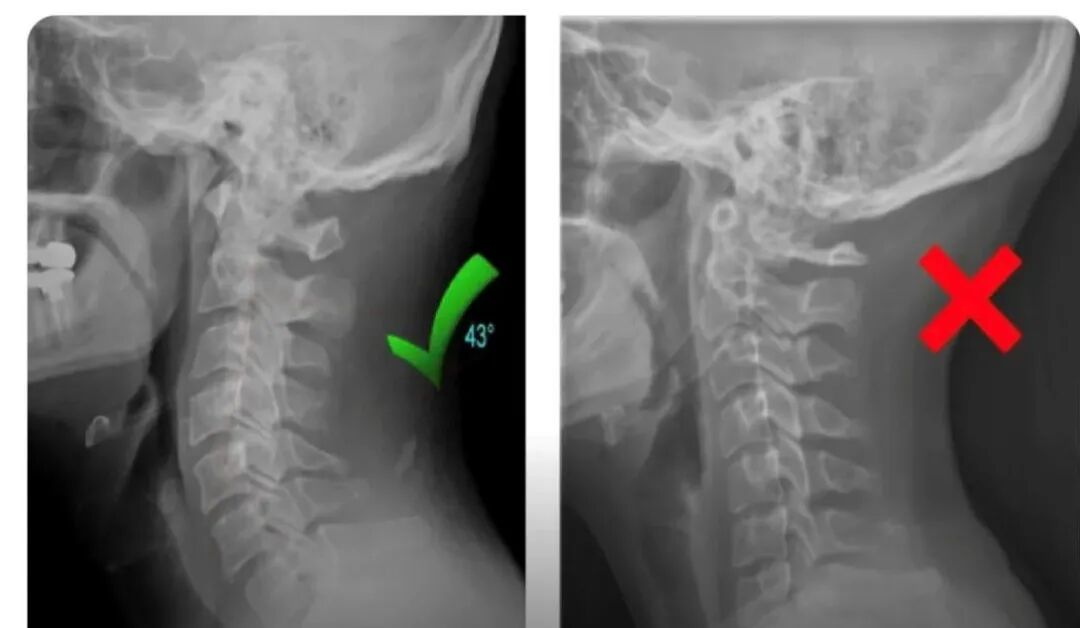

最近一次晚上由于疫情买不到布洛芬,去了医院治疗做了CT,才发现自己的脖子是直着的,,,可以看下面的图。

正常人的脖子是曲线的,青嫂的脖子轻度变形,是直的。如果你经常低头玩手机,平时头痛恶心耳鸣,很有可能也和青嫂一样哦,可以去医院查查。